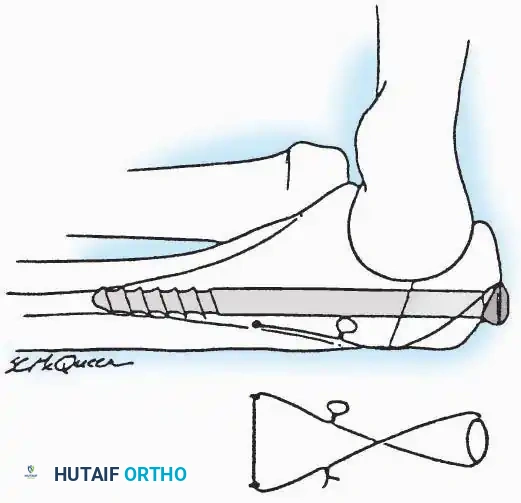

Kocher Approach (Curved L)

Indications: Complete excision of the calcaneus (calcanectomy) for malignant tumors or recalcitrant osteomyelitis.

Surgical Technique:

* Incision: Incise the skin over the medial border of the Achilles tendon, starting 7.5 cm proximal to the calcaneal tuberosity. Extend it distally to the inferoposterior aspect of the tuberosity, curve it transversely around the posterior heel, and continue distally along the lateral surface of the foot to the tuberosity of the fifth metatarsal.

* Deep Dissection: Divide the Achilles tendon directly at its insertion and carry the dissection down to the bone.

* Enucleation: To reach the superior surface, free all tissues beneath the severed Achilles tendon. The calcaneus can then be enucleated subperiosteally or extraperiosteally depending on the oncologic or infectious margins required.